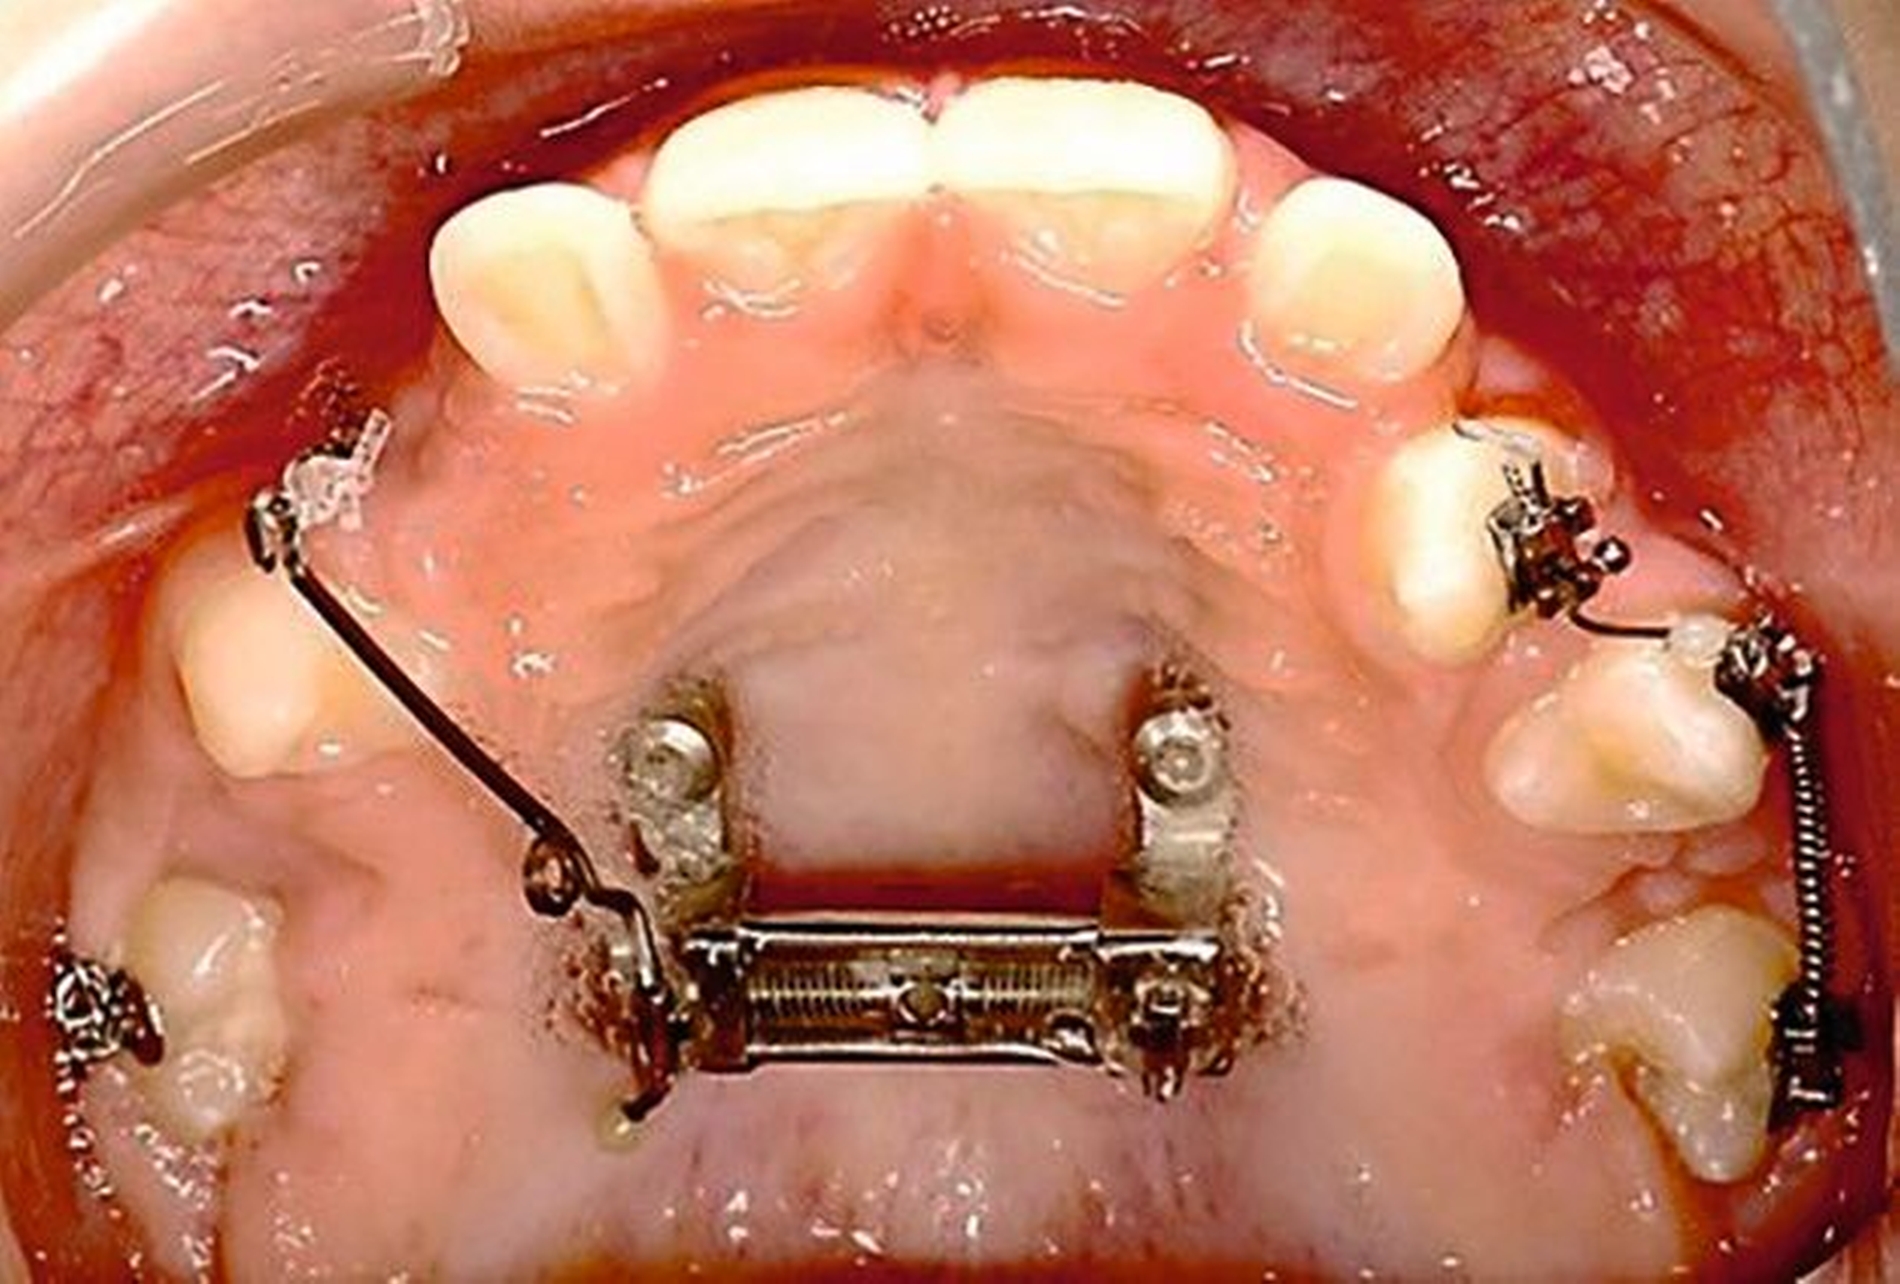

Die Zähne 36, 37, 46 und 47 wurden in Allgemeinanästhesie chirurgisch freigelegt. Zusätzlich wurden die beiden paramedianen Mini-Implantate (2 x 9 mm, Benefit System; PSM North America, Indio, CA) ohne Vorbohren mithilfe der zuvor hergestellten Schablone inseriert (Abbildung 3). Für die Platzierung der Mini-Implantate wurde ein Winkelschraubendreher verwendet. Direkt nach der Operation wurde die bmx DIRECT Hyrax-Schraube (10 mm, BENEfit®-System, Dentalline, Birkenfeld, Deutschland) an den Mini-Implantaten befestigt, um ein MARPE zu erzielen (Abbildung 4).

Die Eltern des Patienten wurden angewiesen, die Schraube einmal täglich zu aktivieren. Die gesamte Aktivierungszeit der Hyrax-Schraube betrug circa zehn Wochen. Während dieser Zeit vergrößerte sich die transversale Dimension des Oberkiefers um sieben Millimeter im posterioren Bereich (Milchmolaren) und um fünf Millimeter im anterioren Bereich (Milcheckzähne). Währenddessen trat ein mediales Diastema auf (Abbildungen 4b und 4c), das auf eine skelettale transversale Expansion des Oberkieferknochens hinwies. Nach der aktiven Expansionsphase der Hyrax-Apparatur wurde das Gerät für weitere Behandlungszwecke verwendet: Erstens als Retentionsgerät, um die bereits erzielte transversale Oberkieferbreite zu halten und zweitens als skelettal verankerte Apparatur zum Einstellen der retinierten und verlagerten Zähne mithilfe individuell angefertigter Kragarme. Hierfür wurde die Hyrax-Apparatur im zahntechnischen Labor modifiziert, indem Kreuzröhrchen für eine stationäre Befestigungen für die Drähte des Kragarms angebracht wurden.